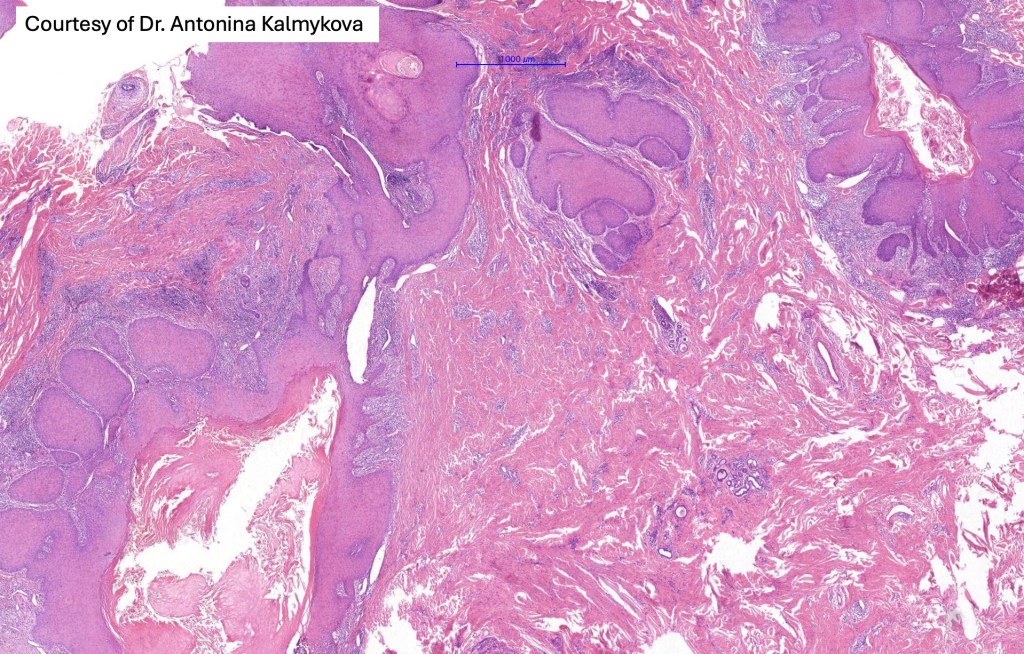

Histological features

•Multilobulated cyst with associated lobules of well differentiated squamous epithelium

•PAS+ve cytoplasmic vacuolation indicating outer root sheath differentiation

•+/- peripheral palisading

•No pleomorphism or significant mitotic activity

•Eosinophilic basement membrane

•Infundibular>trichilemmal keratinization